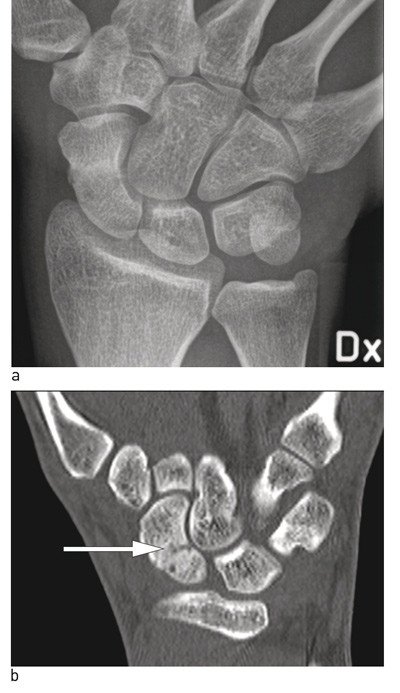

Figure 2  Standard X-ray projections on suspicion of scaphoid fracture, arrow where the fracture is visible. a) Frontal…

Figure 2 Standard X-ray projections on suspicion of scaphoid fracture, arrow where the fracture is visible. a) Frontal projection, b) lateral projection (difficult to identify fracture), c) oblique projection, d) supine projection

Figure 3  Acute scaphoid fracture, not visible on standard X-ray images. a) Frontal projection, overview picture (difficult…

Figure 3 Acute scaphoid fracture, not visible on standard X-ray images. a) Frontal projection, overview picture (difficult to see fracture lines in scaphoid, b) CT we see fracture line, marked with arrow